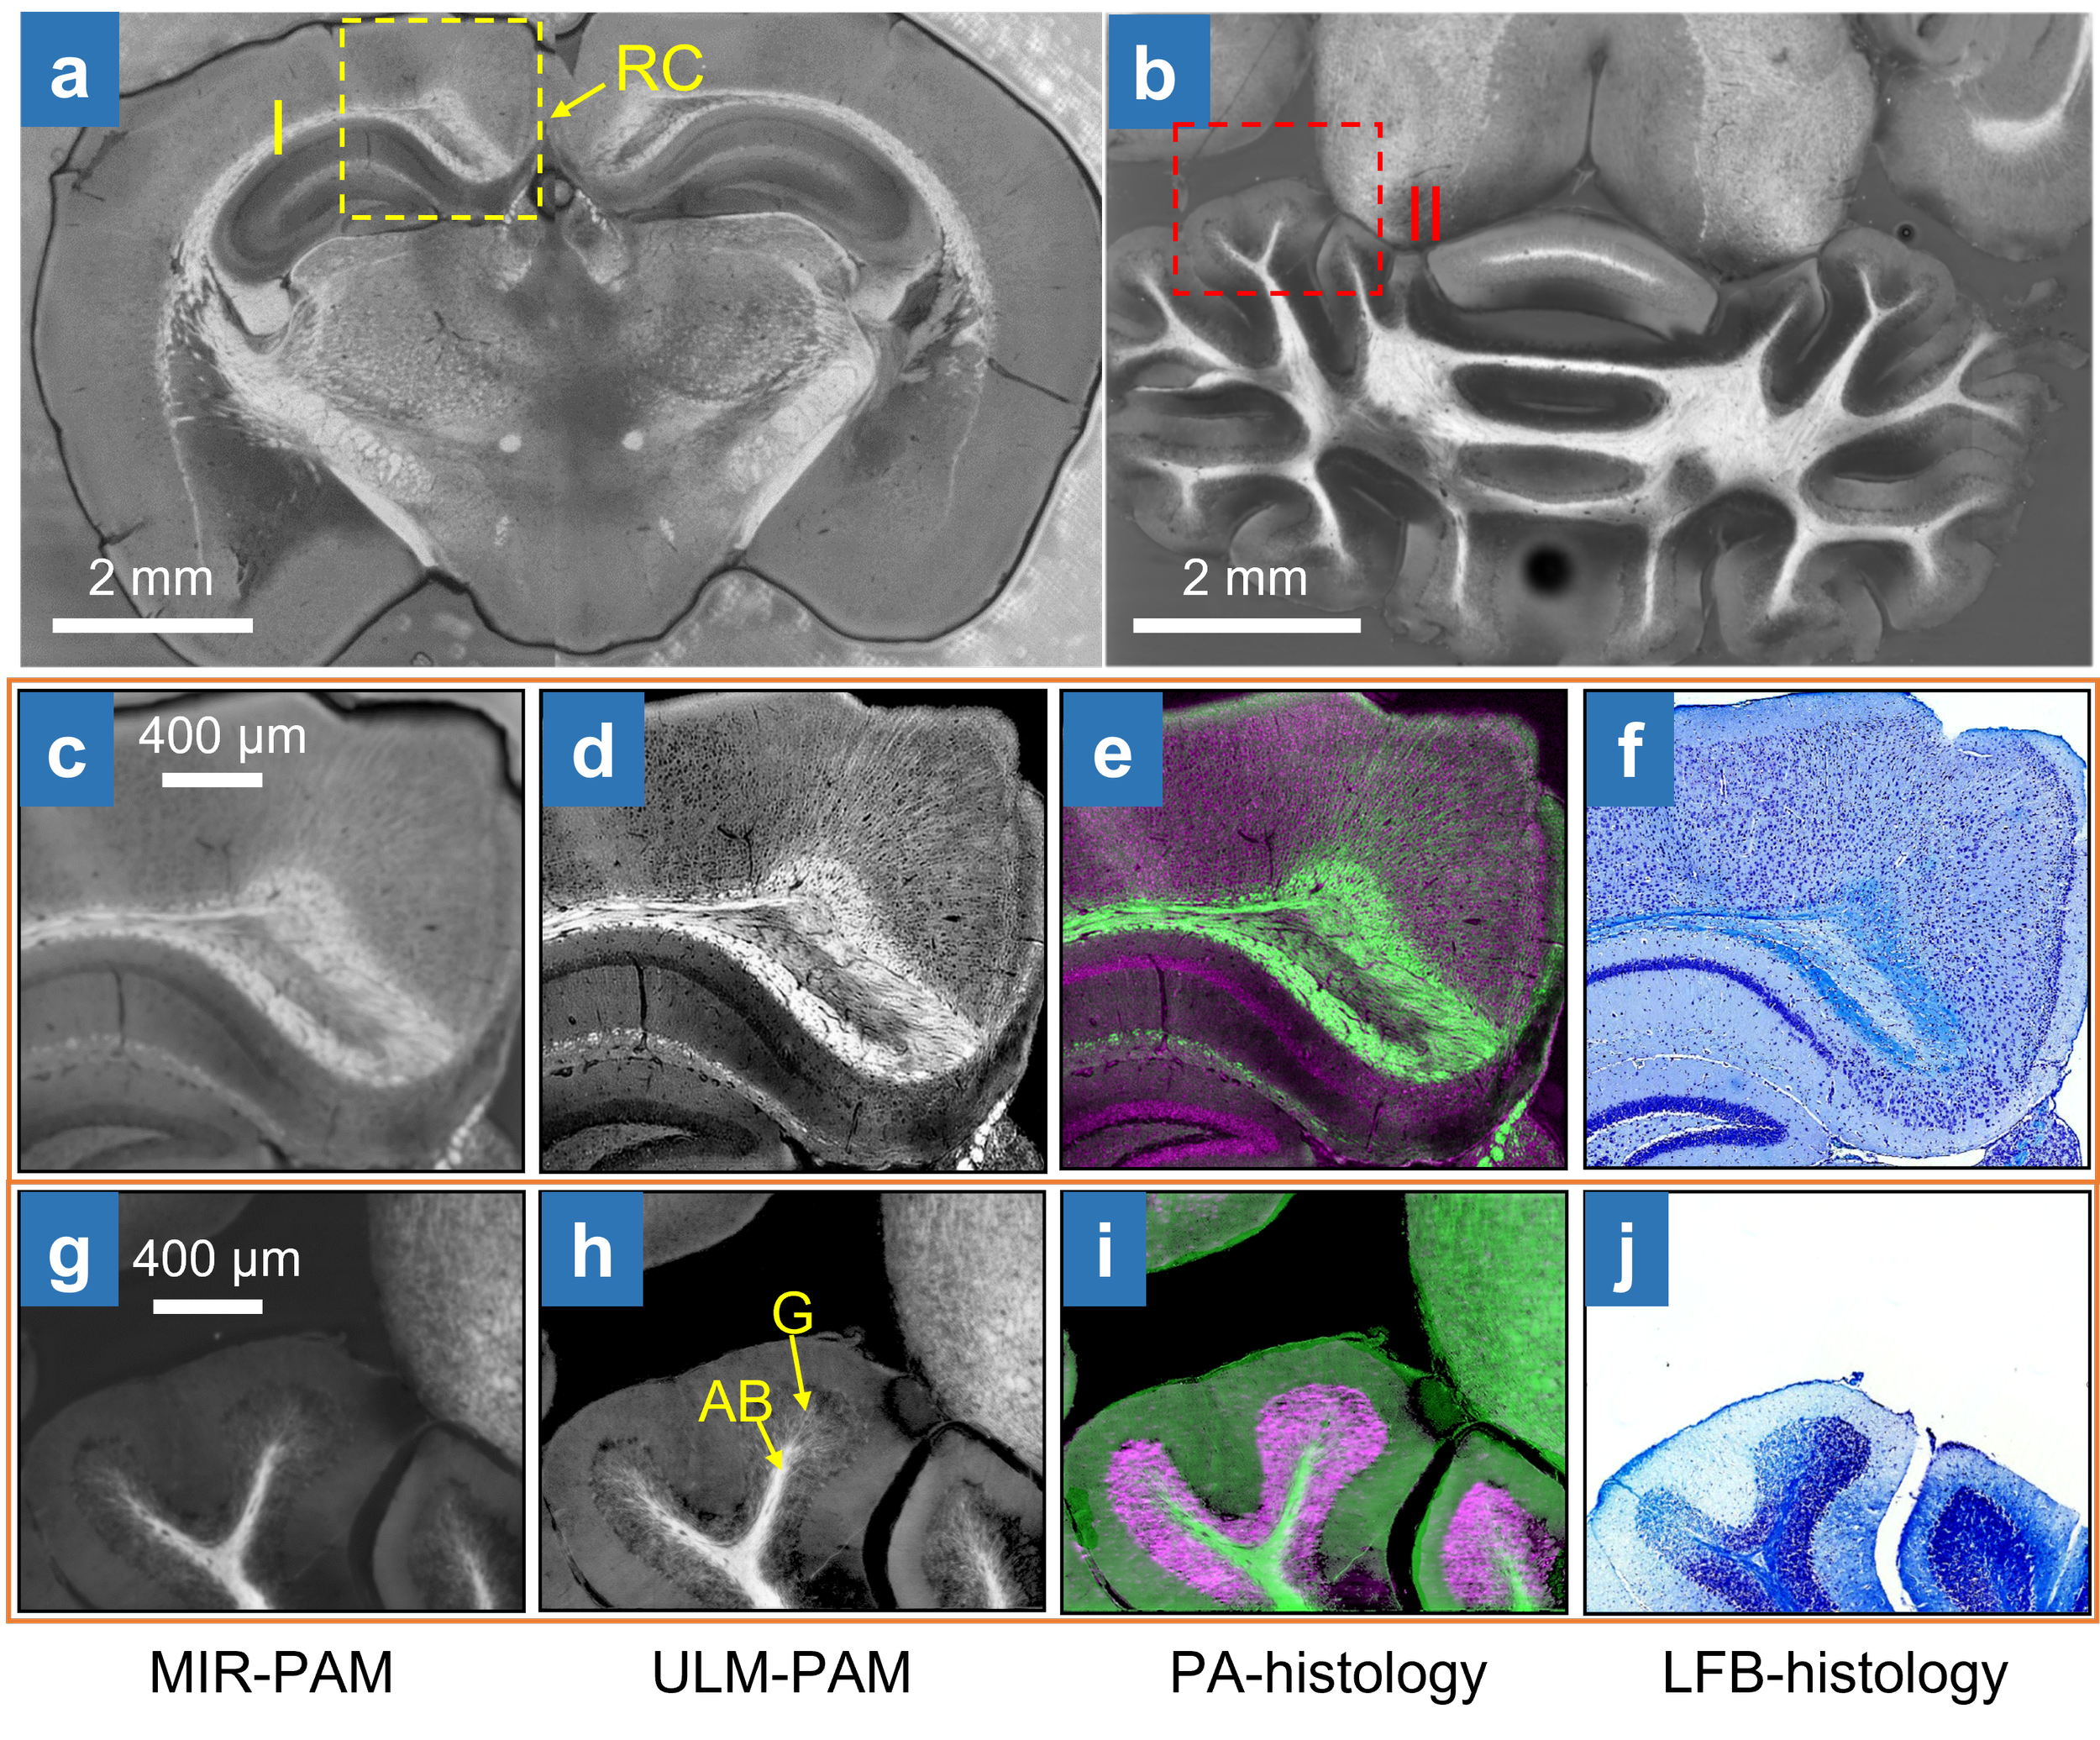

a,b, MIR-PAM images of myelin in slices of the cerebrum (a) and cerebellum (b). RC, retrosplenial cortex. c, Close-up image of myelin. d, ULM-PAM image of myelin. e, PA histology image. f, LFB-stained histology image of the same area (I) in (a). g, Close-up MIR-PAM image of myelin. h, ULM-PAM image of myelin. AB, arbor vitae region; G, granular region. i, Photoacoustic histology image. j, LFB-stained histology image of the same area (II) in (b). In the photoacoustic histology images, green represents myelin and violet represents nucleic acids. In the LFB-stained histology images, blue represents myelin and deep blue represents nucleic acids.